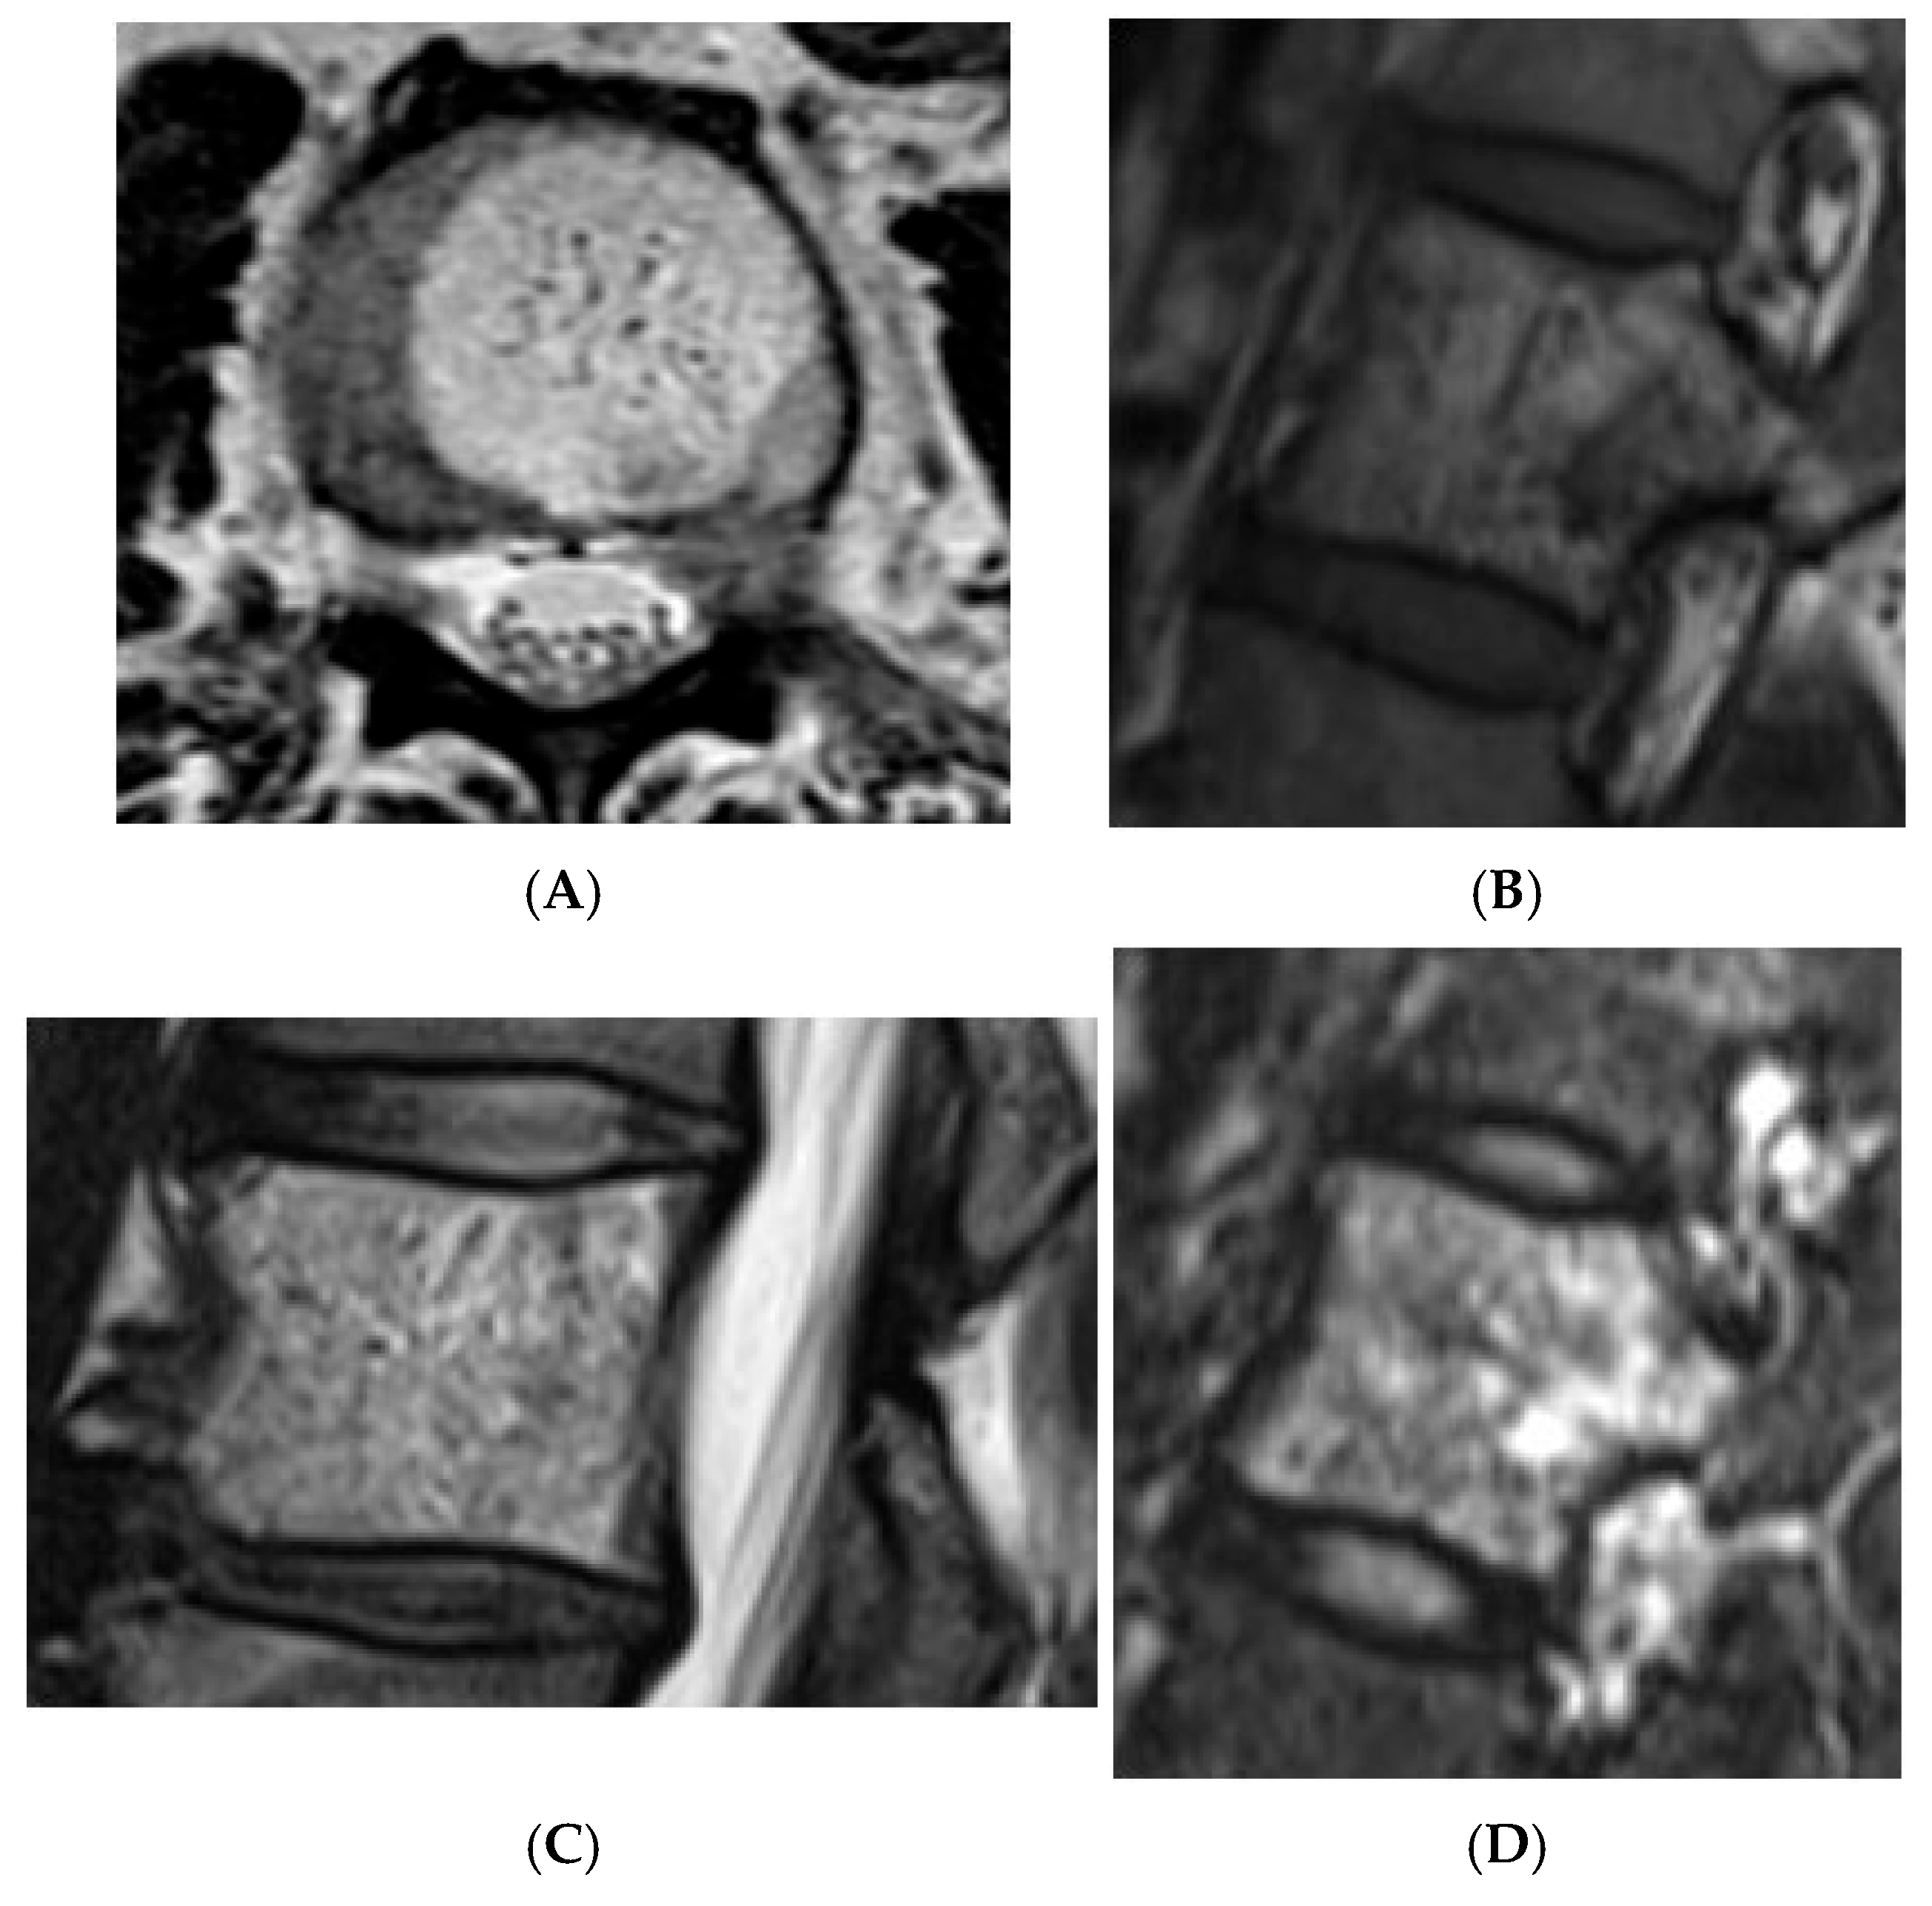

Figure 10.

Typical haemangioma of the vertebral body. (A) T1W axial MRI. (B) T1W sagittal MRI. (C) T2W sagittal MRI. (D) STIR sagittal MRI.